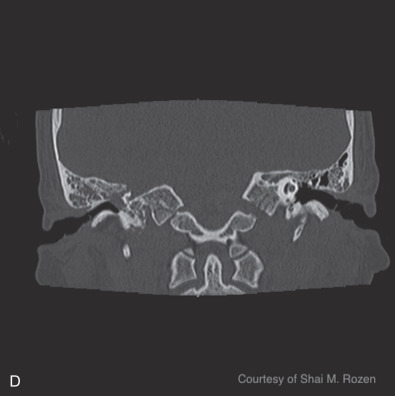

Temporal bone fractures are a product of high-energy blunt trauma commonly resulting in fracture, hemorrhage, nerve trauma, vascular damage, with disruption of the middle or inner ear structures, classically classified into longitudinal, transverse, or oblique fractures. Longitudinal fractures often result from lateral to medial forces extending through the facial nerve canal, possibly causing intraneural hemorrhage, transection, or bone compression. They can disrupt the ossicular chain, resulting in conductive hearing loss. Transverse fractures often result from anterior posterior forces with a fracture line often traversing the vestibulocochlear apparatus causing sensorineural hearing loss and equilibrium disorders. Transverse fractures more commonly injure the facial nerve due to proximity to the nerve’s labyrinthine segment. Oblique, also termed mixed, fractures include both longitudinal and transverse components. Additional classifications are based on degree of involvement of the petrous portion of the temporal bone, or the otic capsule. Temporal bone computed tomography (CT) scans should be performed in thin-section 1 mm cuts to avoid interpreting normal suture lines as fractures.

Blunt injuries resulting in temporal bone fractures are often encountered in motor vehicle accidents, altercations, or falls from heights. Approximately 7%–10% of temporal bone fractures result in facial nerve injury. Temporal bone fractures have several classifications. Fracture line orientation relative to the petrous bone defines fractures as longitudinal (70%–80%), transverse (10%–20%), and oblique (10%). Facial paralysis occurs most commonly in transverse fractures (50%) but may also occur in longitudinal fractures (25%). More modern CT-based classifications assess whether fractures are otic capsule sparing or violating, the latter being twice as likely to cause facial paralysis. Four types of facial nerve trauma have been found in temporal bone fractures. In 76% of longitudinal fractures either bony impingement or intraneural hematoma was found, and in 15% the nerve was transected. In the remainder of patients, no visible pathology was found other than neural edema. In transverse fractures, 92% were transected and 8% had impingement ( Fig. 1.5.3 ). Similar to penetrating intracranial facial nerve injuries, surviving patients are initially often in critical condition and the facial paralysis is often unnoticed.